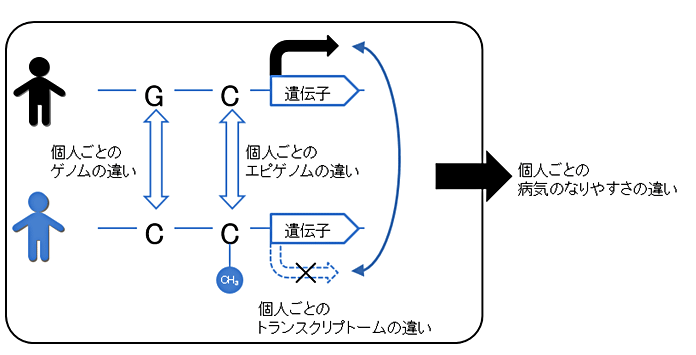

医療・健康 いわて東北メディカル・メガバンク機構、100人規模の全ゲノム・エピゲノム・トランスクリプトーム情報の分譲開始

個別化医療・個別化予防に貢献可能2018-03-30 岩手医科大学 いわて東北メディカル・メガバンク機構,国立研究開発法人 日本医療研究開発機構研究のポイント岩手医科大学いわて東北メディカル・メガバンク機構(IMM)は、生体情報解析部門を中...